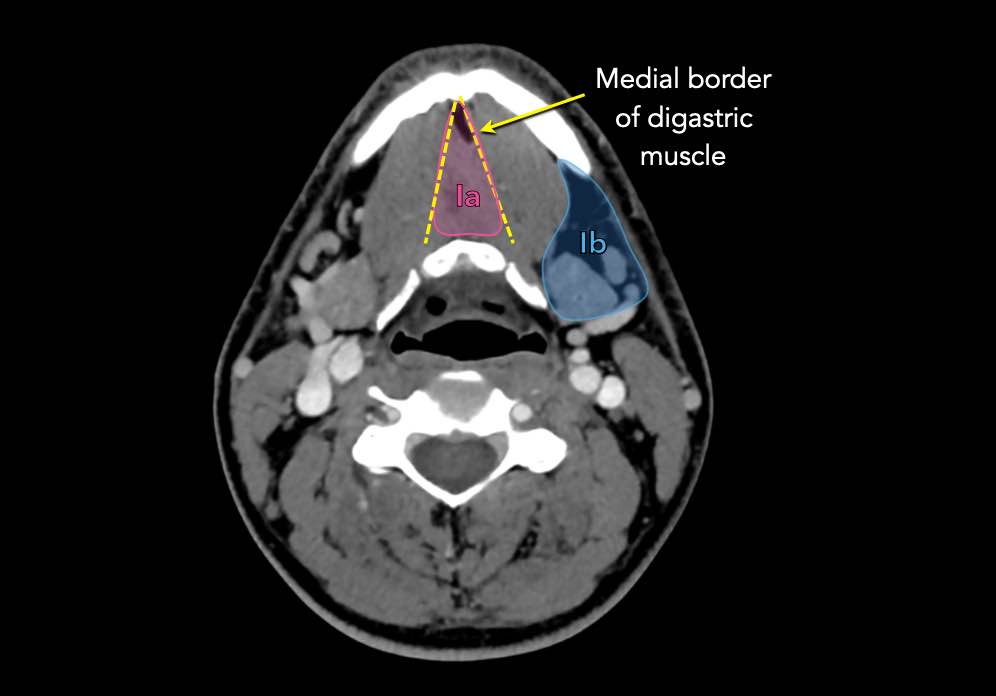

Tầng Ia

là vùng giữa nằm giữa bụng trước của các cơ nhị thân, chứa các hạch dưới cằm.

Tầng Ib

chứa các hạch dưới hàm nằm trong khoang giữa mặt trong của xương hàm dưới ở phía ngoài và cơ nhị thân ở phía trong, từ khớp mu cằm ở phía trước đến tuyến dưới hàm ở phía sau.